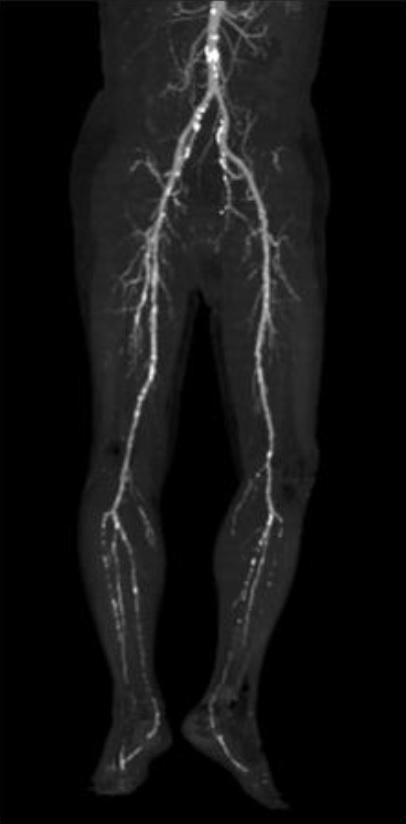

●下肢動脈超音波検査

超音波検査で腹部〜足の動脈の流れを調べます。

超音波検査器で腹部〜足の動脈の狭窄を調べます。

●下肢CT血管造影検査

血液の流れを調べる検査です。